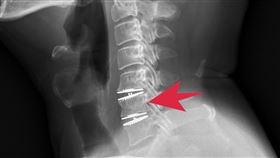

AI上呼吸道檢測+微創手術助患者找回健康

天氣變化大,睡眠呼吸中止症患者增加。台中一名林小姐經...